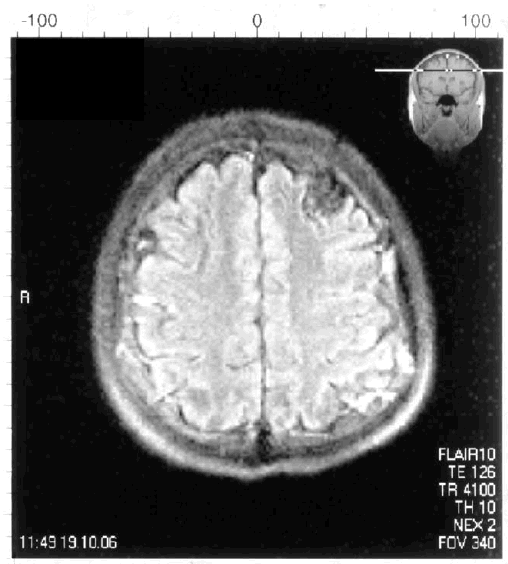

Наличие артериовенозной мальформации левой лобной доли у пациента молодого возраста сопровождалось возникновением УКР и картиной симптоматической эпилепсии (рис. 6.3).

Иллюстрация к книге — Деменция. Диагностика и лечение [i_006.jpg]

Рис. 6.3. Артериовенозная мальформация левой лобной доли у пациента молодого возраста с УКР